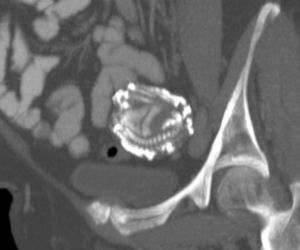

Przypadki „dzieci z kamienia” opisywano już w X wieku